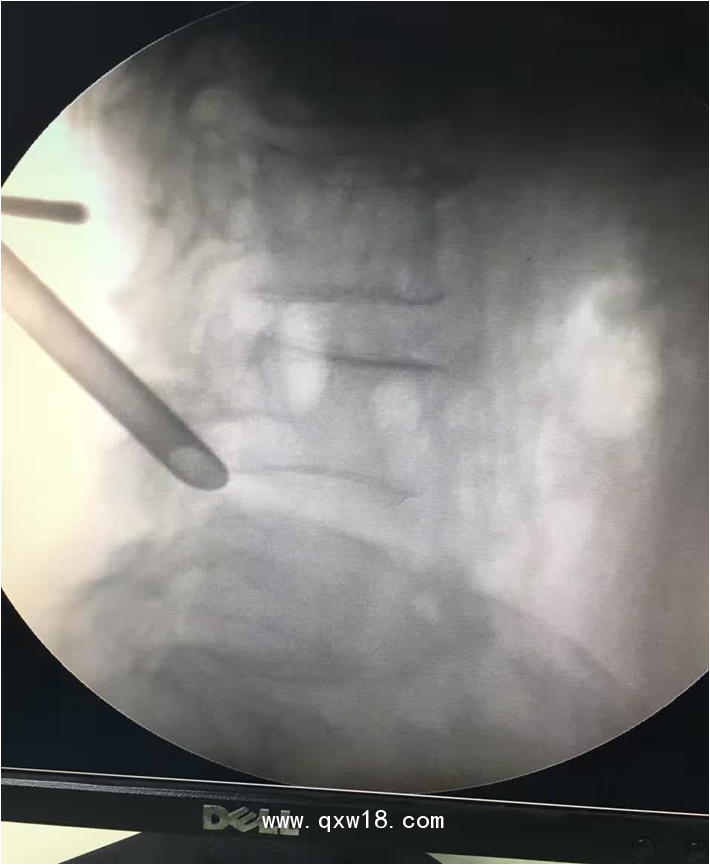

椎間孔鏡品牌椎間孔鏡椎間孔鏡技術(shù)椎間孔鏡培訓(xùn)產(chǎn)品說明:

portant; word-wrap: break-word !important;">椎間孔鏡手術(shù)圍手術(shù)期注意事項(xiàng):